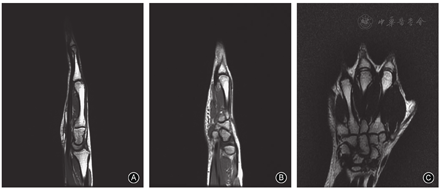

保守治疗2个月后患者右手局部疼痛症状逐渐缓解,口服镇痛药物逐渐减量,4个月后疼痛症状明显改善,右手第3、4掌指关节屈伸活动度逐渐增加,X线片示掌骨头骨质坏死病变无明显进展。半年后门诊复查,患者右手无明显疼痛症状,右手第3、4掌指关节屈伸活动约为85°-10°,右手抓握力约为健侧的90%。治疗后2年,右手各指疼痛评分均为0分、DASH评分为0,右手3、4指掌指关节屈伸活动恢复正常(88°-0°),与对侧无明显差异;无明显骨擦感、骨擦音,右手抓握力为健侧的105%,功能恢复正常(图3)。X线片示右手各指掌指关节正常,第3、4掌骨头关节面变平明显改善、关节面基本恢复,局部骨质硬化改变消失,无明显骨质增生、关节退变表现(图4)。MRI示右手第3、4掌骨头无骨髓水肿挫伤表现,无关节积液,关节面平整,无明显塌陷破坏(图5),提示坏死掌骨头有关节重塑再生。

掌骨头缺血性坏死目前尚无标准的治疗方案和最佳方法。多数病例报告最初都采用了保守治疗,包括休息、关节制动、非甾体抗炎药、电刺激等理疗方法,但治疗成功的案例较少[2,3,26]。1例因肾病综合征使用激素治疗的掌骨头缺血性坏死患者,没有任何局部疼痛症状,也未采取任何的治疗措施,但随访时发现掌骨头缺血性坏死后完全再生[5]。另1例14岁男孩的掌骨头缺血性坏死采取保守治疗后,X线检查也显示了明显的掌骨头自发性重塑[2]。因此,掌骨头缺血性坏死可能是一种自限性疾病,实际的发病例数远比文献报道的多。保守治疗的疗程尚不明确,有患者仅接受了3个月的非手术治疗就改为手术治疗[10]。在另一篇文献报道中4例患者都采取了3~6个月的非手术治疗,仅2例患者掌指关节活动度恢复、疼痛症状改善[3]。青少年掌骨头缺血性坏死保守治疗的疗程可能需要更长,特别是对有多发病灶者;青少年患者骨的重塑和生长能力较强,掌骨头非负重区的缺血性坏死可能会经历自发性的改善和重构。本例患者经4个月的保守治疗,2年后MRI观察到病变掌骨头有良好的重建和再生。因此,鉴于骨重塑的潜力,我们认为青少年掌骨头缺血性坏死患者可以通过保守治疗恢复[2,13,19]。

虽然掌骨头缺血性坏死罕见,但对有掌指关节局部疼痛、活动受限的患者应考虑此病,尤其是有隐匿创伤病史的青少年患者。MRI是诊断掌骨头缺血性坏死比较敏感的方法,不仅可以评价坏死病灶的范围及程度,而且能评估病变的重建和再生。青少年患者骨骼有更强的自我修复能力,保守治疗应该是掌骨头缺血性坏死的首选治疗方式。